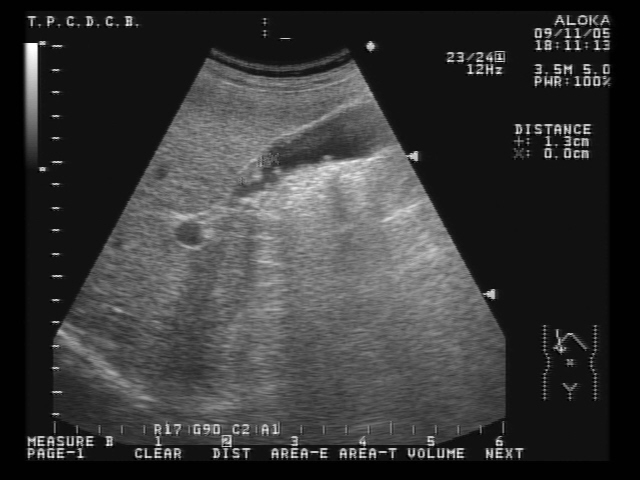

膽息肉很多也都是健檢時或超音波檢查其他腹部器官時不小心被發現

因為一般較小的(小於1公分)膽息肉惡性機率很低,建議可先定期腹部超音波追蹤即可。

若是大於1公分以上的息肉,即須與外科醫師討論是否需進行膽囊切除。

大多數的息肉都是很多小小顆(小於1公分),有柄、類似女王頭那種形狀,良性的機率高,很少與膽囊癌相關。

但超音波下若息肉大於1公分、有寬的基底、膽囊壁局部增生及變厚即要小心可能會有惡性的變化。